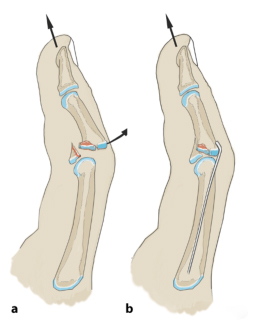

1. Схема модели чрескожной операции по уменьшению и фиксации стальными штифтами:

Применяют методику репозиции Хинтрингера и Эндера: сжатый костный фрагмент удаляют из костномозговой полости через дорсальное костное окно. Потяните вперед и согните проксимальный межфаланговый сустав на 20–30 градусов, чтобы уменьшить подвывих. Зафиксируйте костный фрагмент и проверьте устойчивость пальца в разогнутом положении. Если сохраняется тыльный подвывих средней фаланги, необходимо также заблокировать шкив, в котором в фалангу вводится стальной штифт.

Разрез производят дорсально от средней фаланги в сухожильном треугольнике. При продольном вытяжении (стрелка) палец сгибается на 20–30°. Просверлите отверстие через разрез, наклонив его проксимально (изображение ниже).

Согните один конец 1-миллиметровой проволоки на 30°, чтобы придать ей форму хоккейной клюшки. Затем его вводят в костномозговую полость через просверленное отверстие.

Сокращение суставной поверхности и подвывих при вытяжении. Изогнутая проволока занимает примерно четверть площади соединения. Проксимальная суставная поверхность играет здесь вспомогательную роль.